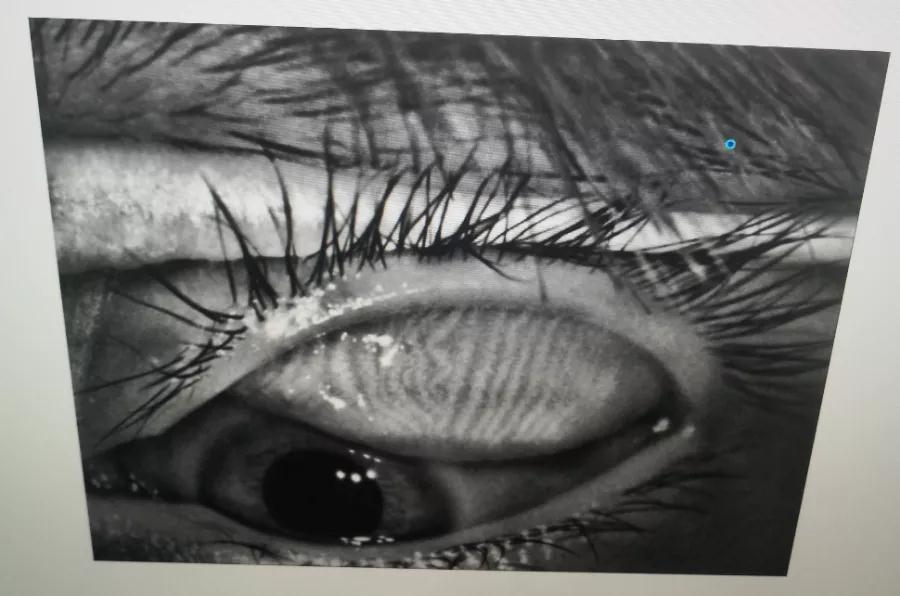

瞼板腺是排列在我們上下眼皮里面,分泌油脂的腺體,這些油脂是組成淚液的重要成分,可以讓淚水更長時(shí)間的停留在眼球表面。瞼板腺油脂減少,淚水蒸發(fā)就會(huì)加快,眼球暴露在外的時(shí)間變長,會(huì)加重眼睛干澀,時(shí)間一久,干眼也就隨之而來。

通過熱敷并按摩擠壓上下眼瞼,將瞼板腺內(nèi)不能自行排出的分泌物推出,疏通堵塞的瞼板腺開口。

熱敷可以促進(jìn)眼周部位的血液循環(huán),瞼板腺按摩能有效改善瞼板腺功能,解決絕大多數(shù)干眼患者油脂分泌不足問題。

03、OPT強(qiáng)脈沖光

通過強(qiáng)脈沖光高溫消除蠕形螨蟲,同時(shí)脈沖光產(chǎn)生的熱量可以熔解軟化瞼酯,改善瞼板腺內(nèi)脂質(zhì)分泌物的流動(dòng)性,疏通瞼板腺,提高淚膜的穩(wěn)定性,恢復(fù)正常眼表功能和眼部“鎖水”能力,從病因上治療干眼。